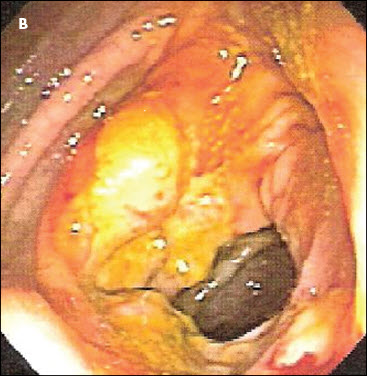

The patient had tenderness in the right upper quadrant, without signs of peritonism. A CT scan with contrast of the abdomen and pelvis demonstrated an apple core lesion (A). Colonoscopy revealed an ulcerated mass in the ascending colon, which strongly suggested malignancy (B). However, a biopsy specimen of the lesion showed only inflammatory changes with areas of ulceration (C).